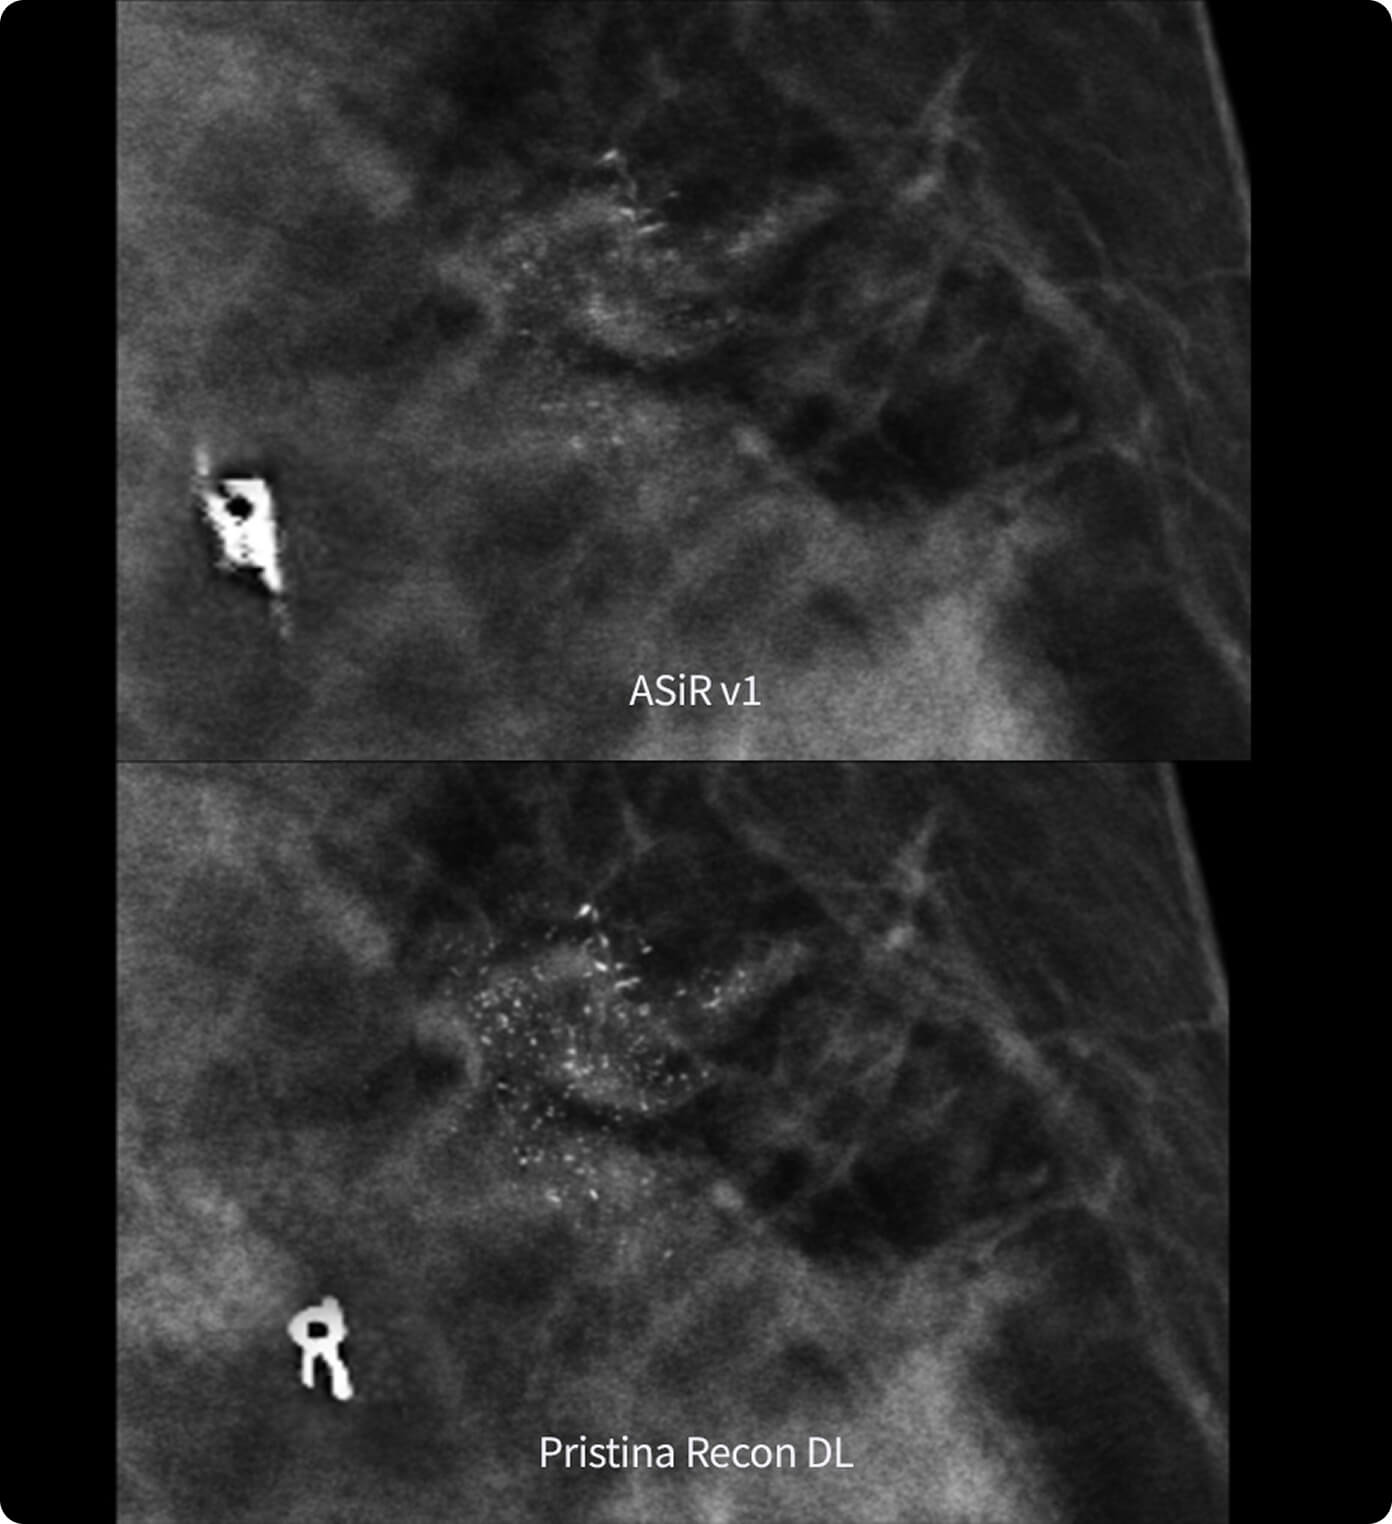

В видеоролике представлен практический опыт внедрения технологии Air Recon DL (ARDL) — технологии реконструкции МР-изображений на основе алгоритмов глубокого обучения. В отличие от традиционных методов постобработки ARDL позволяет значительно снизить уровень шума, повысить пространственное разрешение и четкость изображений без увеличения времени сканирования.